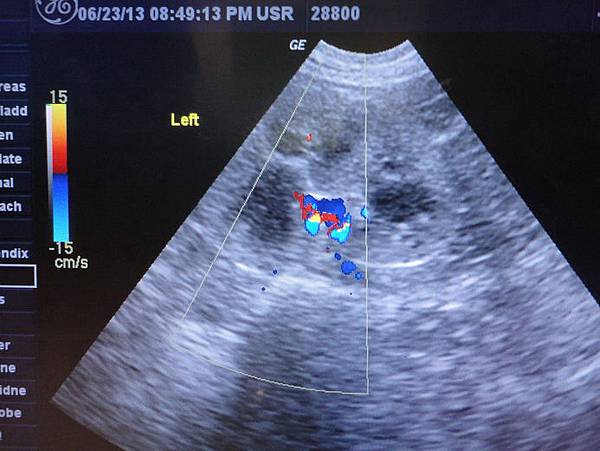

還看了一下腎臟血液的狀況

大致上還正常,但有老化的跡象